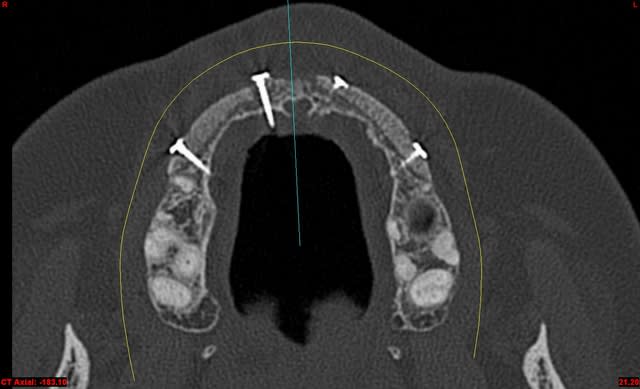

dentiste57 écrivait:

--------------------

> et là ?

> greffe selon ta méthode ?

Cross section dhvkc8 - Eugenol

3d dt3qom - Eugenol

Overview uqcp6u - Eugenol

S2y2o1v7q53ws4r5wy6ou8czrpom - Eugenol

pxav

01/05/2011 à 12h55

> dentiste57 écrivait:

> --------------------

> > et là ?

> > greffe selon ta méthode ?

expansion, c'est plus cool!